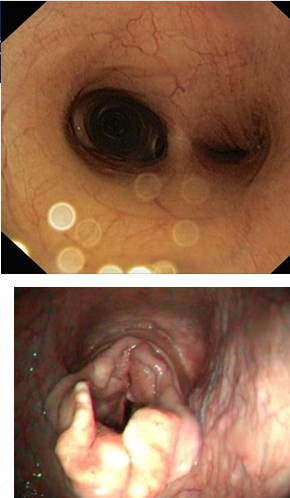

What is being shown here

Mucus accumulation

What are the types of wheezes?

Polyphonic wheeze

Monophonic wheeze- single sound (in image)

What does this show?

non septic

LRT inflam

neutrophils (not degenerate)